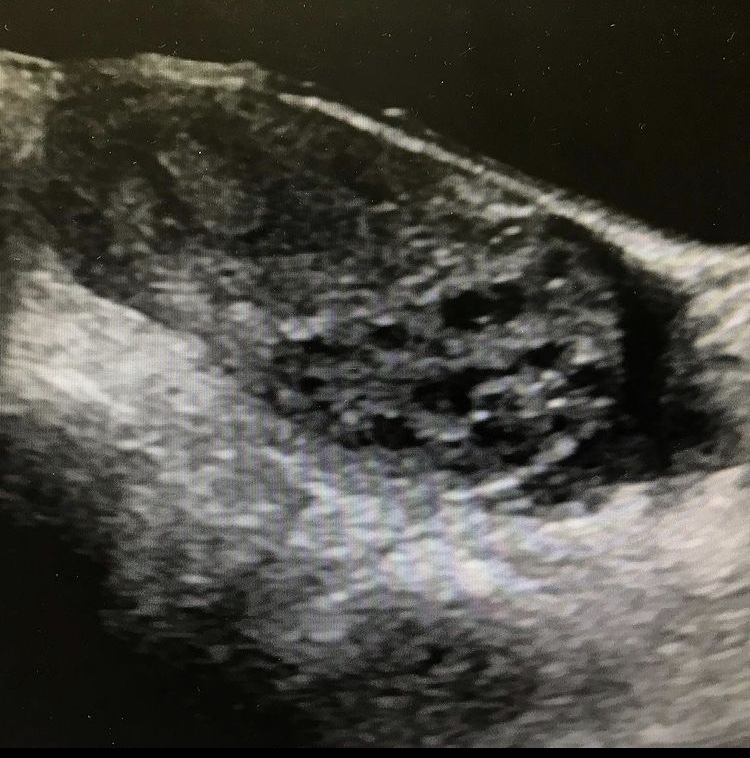

Case #3

Right ovarian torsion caused by hemorrhagic cyst